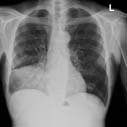

X-ray of a patient with a collapsed lung.

Frontal x-ray of the chest showing a collapsed left lung.